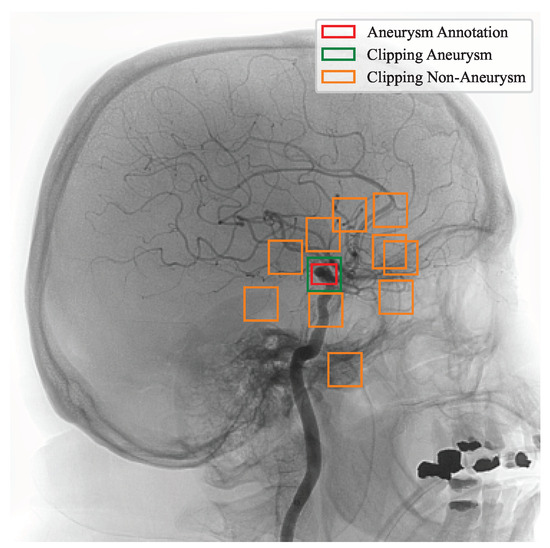

All cropped images pass by zero-mean normalization. Thus, the original 10-bit grayscale pixel was converted from an original range of 0–1023 to a unit value and shifted by the mean value to a final range from −0.5 to +0.5. Figure 6 illustrates the procedure we used to cut the data for aneurysms and non-aneurysms from the original image. The red rectangle represents the original annotation. For the purpose of training the model, it is inconvenient for us that the annotation region has different dimensionality for different images, patients, and aneurysm sizes. For training, we used a square region centered by the original annotation. It is shown by the green square. Around the annotation, we clipped non-aneurysm vasculars. If a random cut interfered with the annotated region, we ignored it and replaced it with another cut. Because there are disproportionately more healthy vessels, we limited the number of non-aneurysm clippings to 10.

Figure 6. Example of data clipping.